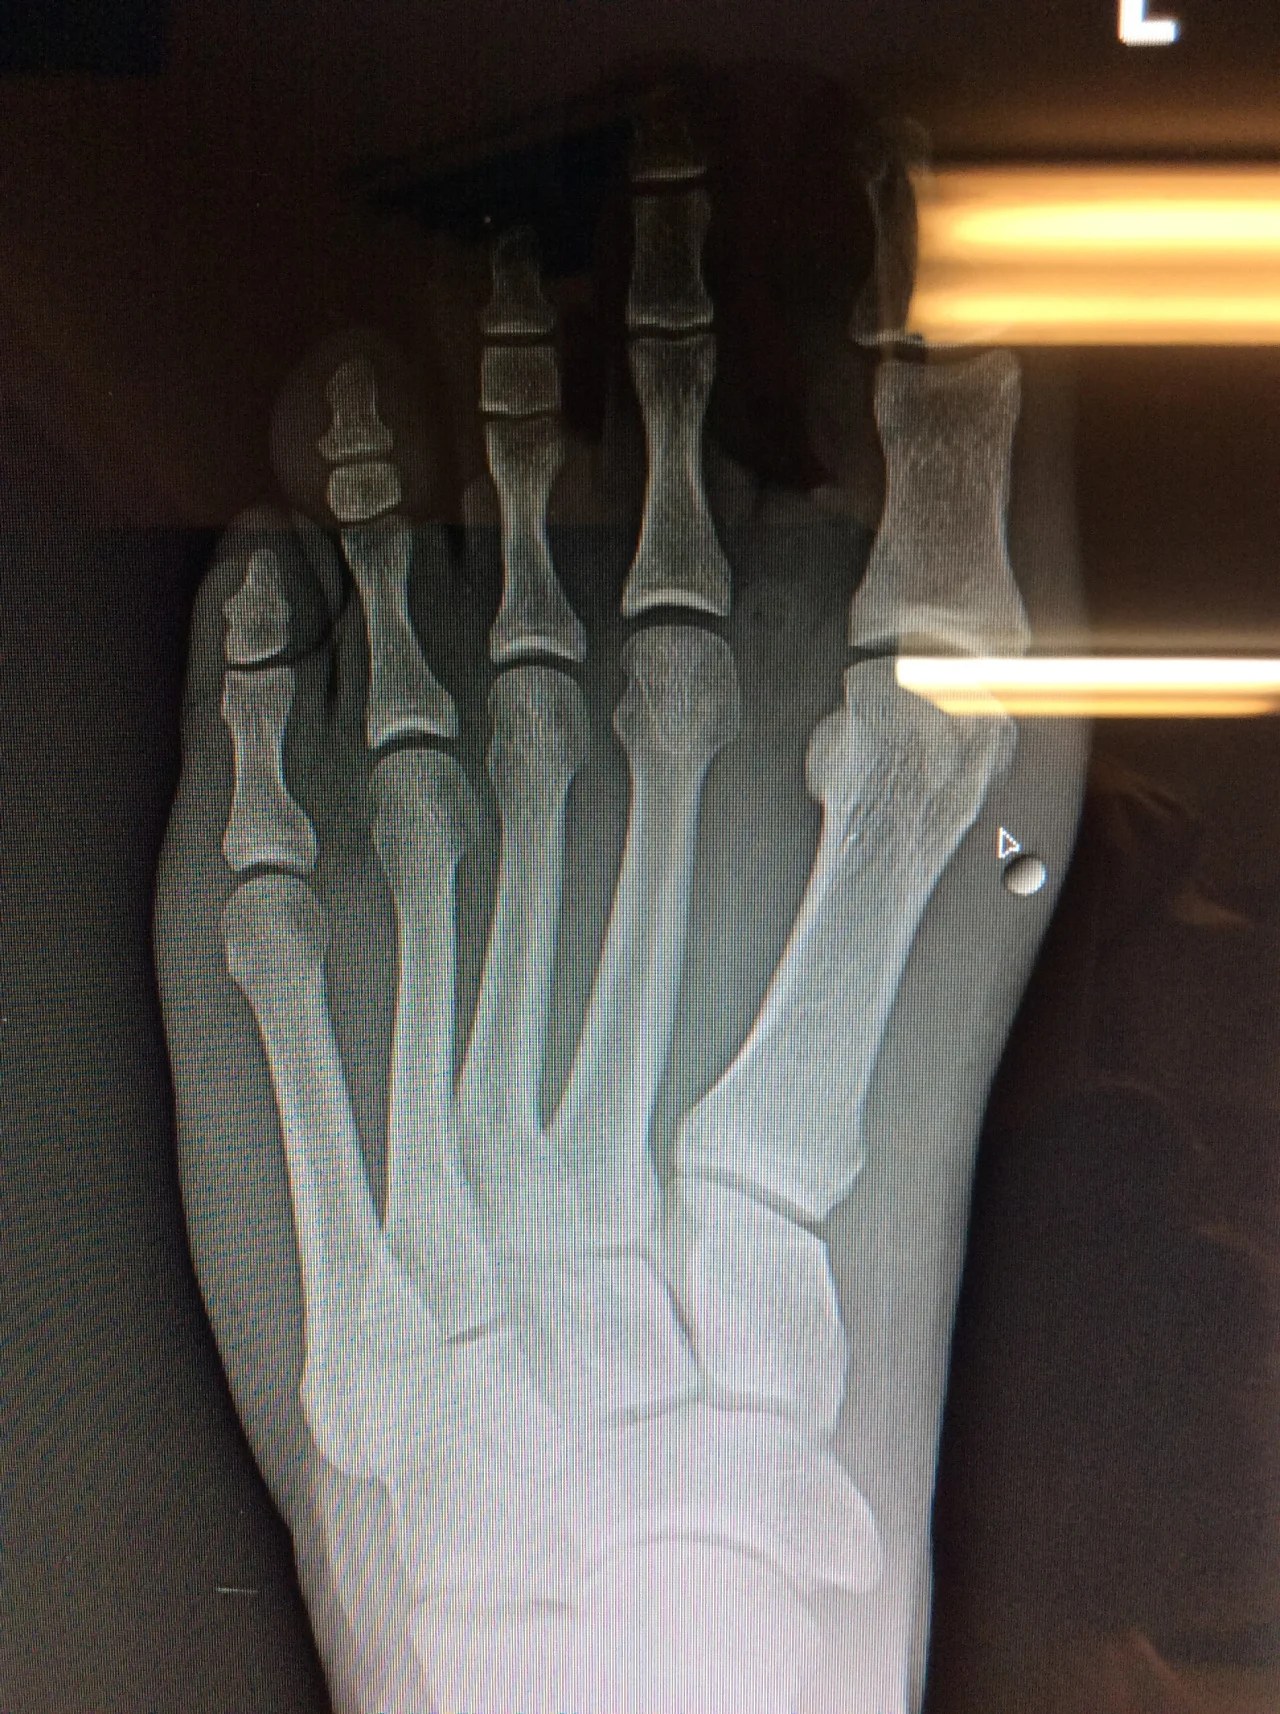

Examination revealed some redness mild swelling over the 1st metatarsophalangeal joint (see pictures above) and hallux dorsiflexion of 10°. If we raised the base of the first metatarsal and pushed down on the head of the 1st, he was able to dorsiflex the 1st MTP approximately 50°. He had point tenderness over the medial sesamoid. We shot the x-rays you see above. The films revealed a fracture of the medial sesamoid with some resorption of the bone.

The sesamoid fracture caused the head of the 1st metatarsal to descend on one side, and remain higher on the other, altering the axis of rotation of the joint and restricting extension. We have talked about the importance of the axis of this joint in may other posts (see here and here).